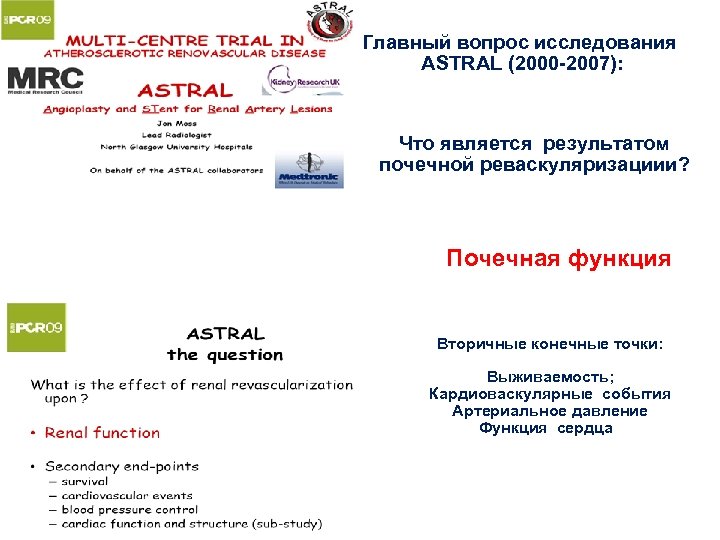

Главный вопрос исследования ASTRAL (2000 -2007): Что является результатом почечной реваскуляризациии? Почечная функция Вторичные конечные точки: Выживаемость; Кардиоваскулярные события Артериальное давление Функция сердцаа

Главный вопрос исследования ASTRAL (2000 -2007): Что является результатом почечной реваскуляризациии? Почечная функция Вторичные конечные точки: Выживаемость; Кардиоваскулярные события Артериальное давление Функция сердцаа